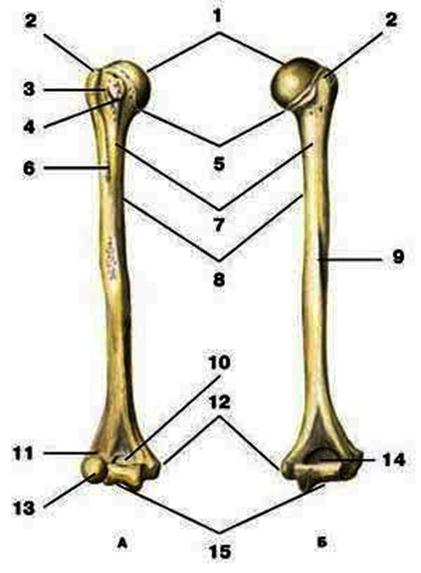

V2:Тема 1.3 Кости верхней конечности и их соединения

S: Цифра 1 обозначает … плечевой кости.

+:сaput

-:t uberculum majus

-:troсhlea

-:capitulum

-:epicondylus lateralis

S: Число 15 обозначает... плечевой кости.

+:trochlea

S: Цифра 5 указывает на...плечевой кости.

+:collum anatomicum

-:collum chirurgicum

S: Число 10 обозначает... плечевой кости.

+:fossa coronoidea

S: Число 14 указывает на... плечевой кости.

+:fossa olecrani

S: Цифра 9 указывает на... плечевой кости.

+:sulcus nervi radialis

S: Число 12 обозначает... плечевой кости.

+:epicondylus medialis